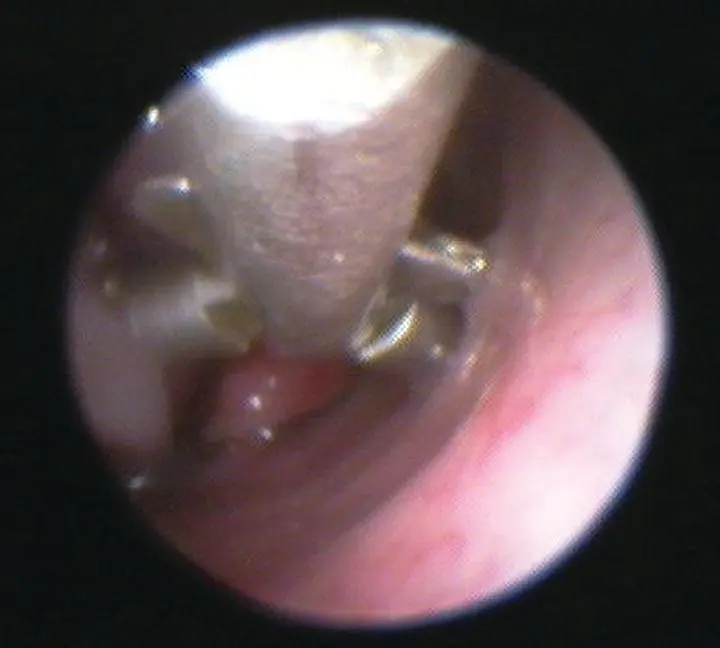

Mass lesions, fungal plaques, and specific mucosal lesions should be biopsied with visualization to improve the probability of achieving a diagnostic sample. With diffuse or generalized disease, an attempt should also be made to obtain at least the initial nasal biopsy with visualization of the area ( Figure 2.13). This can be accomplished either by using a biopsy instrument that fits over the scope, by using a flexible biopsy instrument that passes through the sheathed scope, or by advancing a rigid biopsy instrument along the outside of the rigid telescope. Once bleeding starts, the visual field is usually lost, although intermittent flush and suction can be used to clear the field. Nasal flush can be achieved by attaching a bag of chilled fluids to the biopsy port on the sheath of the scope, or by inserting a red rubber catheter into the nasal cavity and using syringes to obtain a pulsatile pressurized flush. In cats, a 20–60 ml syringe inserted into each naris can be used for nasal flush ( Figure 2.14). Nasal flush should also be used if excessive mucus obscures visualization of the nasal cavity. If a foreign body is highly suspected but is not visualized or removed during the procedure, nasal flush will sometimes dislodge the material. The surgical lap pad protecting the endotracheal tube should be removed, examined for foreign material periodically, and replaced with a new one. Also, if a foreign body is suspected, consider placing a Foley catheter in the caudal nasopharynx and using retrograde flush of the nasal cavities to dislodge items ( Figure 2.15).

Figure 2.13 Diagnostic yield of a nasal biopsy sample is improved when the site to be sampled is visualized during the biopsy procedure.